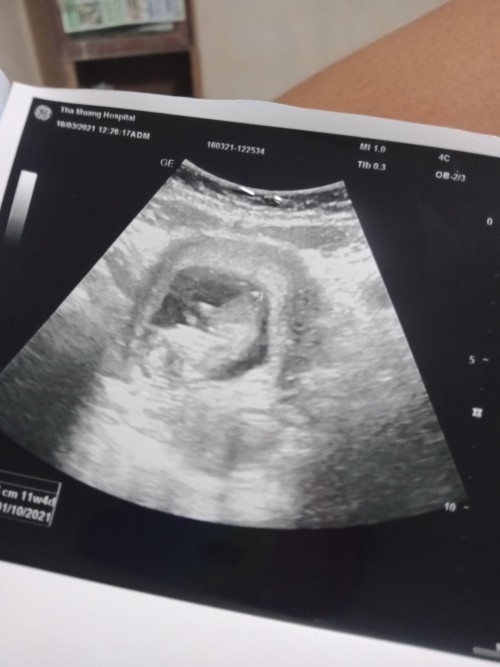

อัลตร้าซาวด์

พอดีวันที่ 13 นี้หมอนัดค่ะ อายุครรภ์วันที่นัดก็ประมาณ 13+4 วีค อยากเห็นภาพอัลตร้าซาวด์ของแม่ๆที่อายุครรภ์เท่ากันหรือใกล้เคียงกันค่ะ ว่าน้องมีพัฒนาการถึงไหนแล้ว ?

12วีคค้าาา🥰